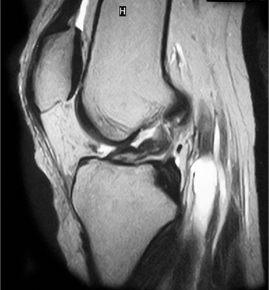

• ACL 손상 방사선 사진4